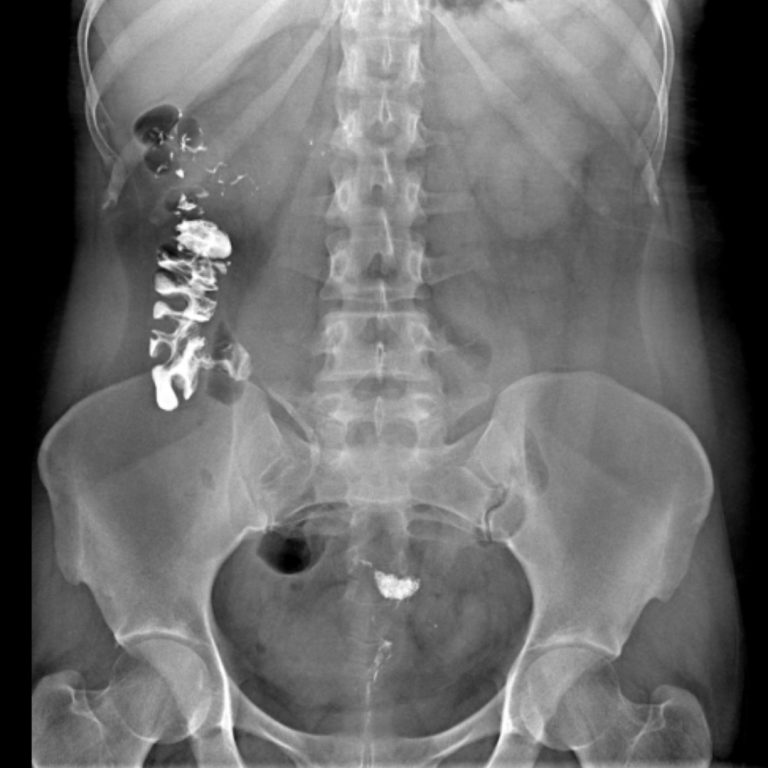

IVP- İNTRAVENÖZ PYELOGRAM

IVP böbrek inceleme filmi, böbrek ve idrar yolları hastalıklarının tanısında başvurulan radyolojik bir inceleme yöntemidir. Bu inceleme Merkezimizde,son sistem C kollu dijital röntgen cihazyla. bu alanda uzmanlık eğitimi almış hekimlerimiz tarafından yapılmaktadır.Böbrekler ve idrar yolları, karın içi organları (özellikle barsaklar) tarafından örtüldüklerinden röntgen filmlerinde net izlenemezler. Onları net olarak görüntüleyebilmek için incelemeye gelmeden önce barsaklarınızın boşaltılması amacı ile önceden “müshil” adı ile tanıdığımız bir ilaç kullanmanız gerekmektedir.Bu amaçla inceleme randevunuzdan önce size tarif edildiği şekilde hazırlığınızı yaptıktan sonra hiçbir şey yemeyerek merkezimize aç karnına gelmelisiniz.

Içecek olduğunuz müshil ilacı sizi geçici olarak ishal yaparak barsaklarınızın boşalmasını sağlayacaktır. Ilaç, etkisini genellikle 8-10 saat içinde göstereceğinden size bildirilen dozların dışına çıkmamanızı öneririz. IVP filminde; böbreklerinizin ve idrar kollarınızın görüntülenmesi amacı ile “Radyolojik Kontrast Ilaçlar” adını verdiğimiz bir ilacın damar yolu ile enjeksiyonu gerekmektedir. Bu ilaçlar “iyot” içerirler ve kana karıştıktan sonra böbrekler tarafından süzülerek, röntgen filminde böbrek ve idrar yollarının görüntülenmesini sağlarlar.

- Sol üreter distal orifis düzeyine superpoze yaklaşık 5 mm çapındaki opasite kalkül açısından anlamlı bulunmuştur. Bunun sonucu geç fazda sol üreter distal 1/3 segmenti vizualize olmuştur ve normalden hafif geniştir. Bununla birlikte sol proksimal üreter ve sol renal pelvikaliksiyel sisteminde patolojik ektazi izlenmemiştir. Bulgular parsiyel obstrüksiyona yol açan üreter orifis kalkülü açısından anlamlı bulunmuştur.

- Sol böbrek orta ve alt kaliksiyel yapılarda sırasıyla 3 mm ve 3.5 mm boyutlarında 2 adet nonobstrüktif kalkül mevcuttur.